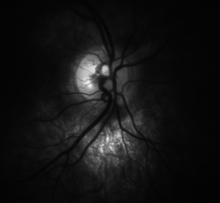

![High detail picture of optic disc [epiCam].](../I/m/Optic_disc_detail.png)

Traditional colour-film camera images are the reference standard in imaging, requiring an expert ophthalmic photographer, ophthalmic technician, optometrist or an ophthalmologist for taking standardised pictures of the optic disc. Stereoscopic images offer an excellent investigative tool for serial follow-up of suspected changes in the hands of an expert optometrist or ophthalmologist. In recent times high resolution real-time video of the optic disc has allowed for the analysis of blood-flow and vasodilation in vessels in the area of the disc (epiCam) which may help to quantify both retinal and systemic disease.